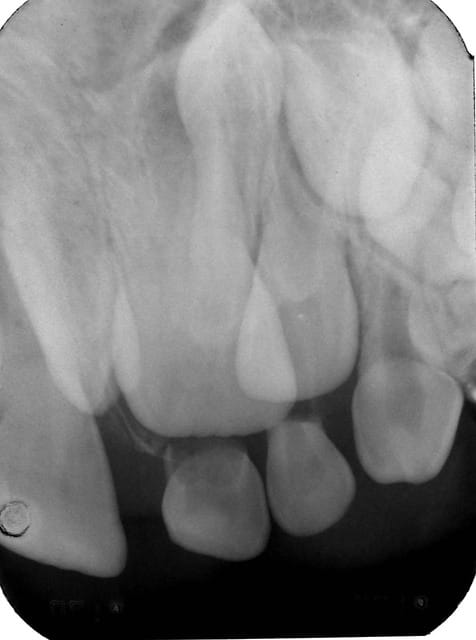

Premier cas , radiographies 11a et 21a ,

chez un garçon de 12 ans .

La 11 est retenue en rotation avec une mésiodens en position palatine .

La 21 est en normoposition avec également une mésiodens en position palatine .

TRT : exerèse des deux dents surnuméraires puis repositionnement orthodontique de 11 .